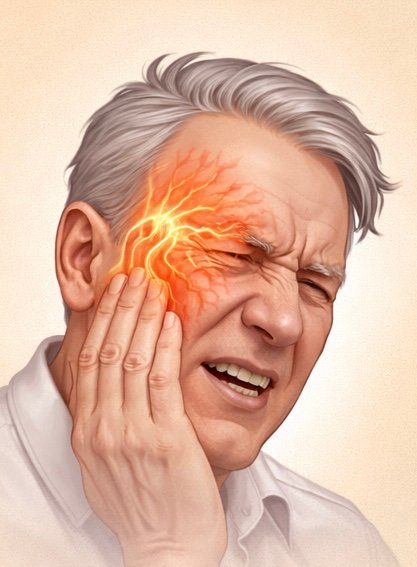

Trigeminal Neuralgia

Trigeminal neuralgia is a severe nerve pain condition affecting the face.

It causes sudden, electric-shock-like pain triggered by activities such as talking, chewing, or touching the face.Advanced treatments including nerve blocks and radiofrequency procedures can help control pain effectively.